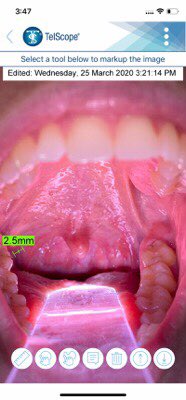

Our new TelScope System enables Intraoral Telehealth between patient and doctor or doctor and specialist. TelScope System can capture an Intraoral image and securely send that image to a doctor, dentist or specialist.

TelScope System can capture an Intraoral image and securely send that image to a doctor, dentist or specialist.